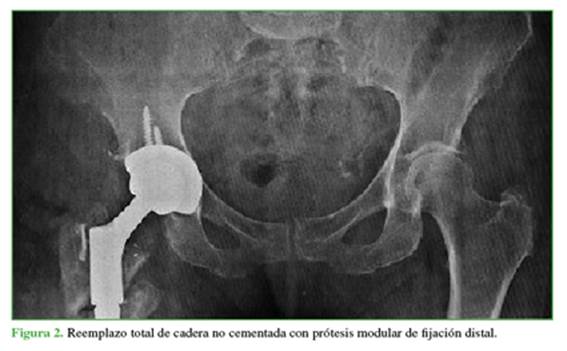

Esta complicación fue tratada con un reemplazo total de cadera no cementado con prótesis modular de fijación distal en 2019 (Figura 2), debido a la pérdida del área de fijación en el fémur proximal.